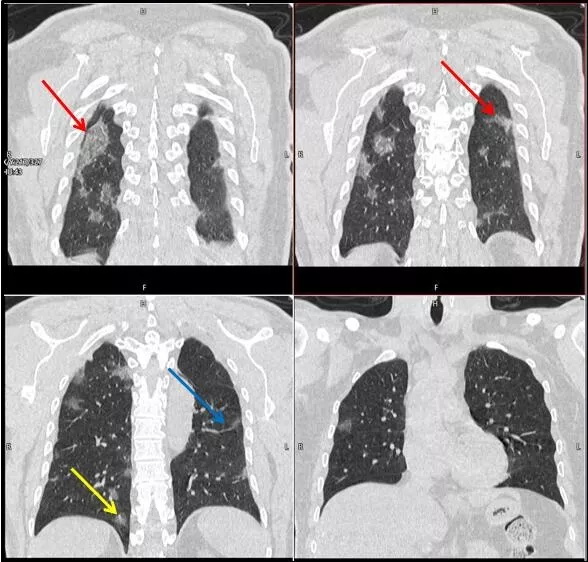

武漢大學(xué)中南醫(yī)院影像科副主任張笑春教授發(fā)現(xiàn),目前武漢市家庭聚集性發(fā)病較多,而且大多起病隱匿,一次甚至多次核酸陰性,無(wú)任何臨床癥狀,CT檢查卻已顯示為病毒性肺炎特征。

為了盡快篩查新型冠狀病毒肺炎患者,醫(yī)院會(huì)選擇影像診斷作為早期發(fā)現(xiàn)新型冠狀病毒感染的肺炎的重要一環(huán)。

CT為當(dāng)前首選篩查與診斷的主要影像學(xué)手段,胸部CT的病毒性肺炎檢出率高。

方舟CT(CT Ark)可以滿(mǎn)足全面的臨床功能,配置16層、32層、64層、128層CT,實(shí)現(xiàn)了低劑量掃描要求,配合NDI微劑量迭代技術(shù),智能毫安調(diào)控技術(shù),使各種場(chǎng)合下、各部位低劑量掃描得以實(shí)現(xiàn);超高分辨率CT病灶靶掃描,使病灶的密度顯示更加精確,能夠顯示病灶內(nèi)輕度的密度變化,有利于小病灶的密度定量分析和及時(shí)診斷。